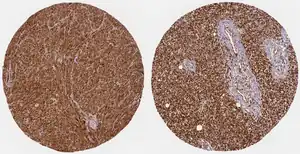

Cancers

WWTR1 (TAZ) is implicated a wide variety of cancers including melanoma, head and neck squamous cell carcinoma, breast cancer, non-small cell lung cancer, and others due to its high gene and histological expression, as well as correlation with increased metastasis and poorer survival in animal studies and patient data.[9] Along with the structurally similar co-regulator YAP, many studies have described their role in promoting oncogenesis, altering neoplastic metabolism, and generating resistance to therapeutic intervention.[8][9][32][33] In particular, TAZ overexpression conferred resistance to cisplatin chemotherapy as well as immunotherapy treatment with a PD-1 antibody.[32]